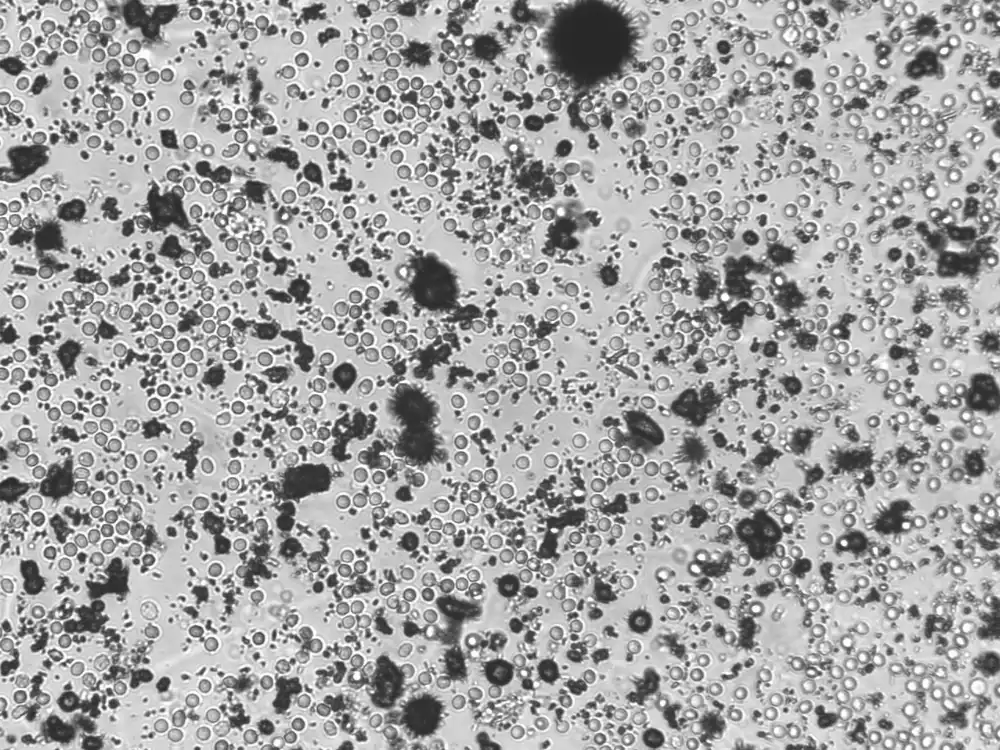

Ammoniumuraatkristallen zijn zeldzame kristallen die voorkomen in alkalische of neutrale urine, meestal bij aanwezigheid van ammoniak, geproduceerd door urease-producerende bacteriën zoals Proteus of Ureaplasma. Ze hebben een kenmerkend uiterlijk: geel- tot bruingekleurde, bolvormige structuren met stekelige uitsteeksels (“doornen”). Deze kristallen ontstaan vaak in urine die langdurig heeft gestaan, of in urine met een hoog ammoniakgehalte, bijvoorbeeld bij een urineweginfectie. Ze vertonen sterke birefringentie onder gepolariseerd licht, maar zijn klinisch meestal van geringe betekenis. Visueel kunnen ze worden verward met onder andere leucinekristallen, die eveneens geelbruin zijn, maar een radiaal, concentrisch patroon vertonen zonder uitsteeksels.

Individueel